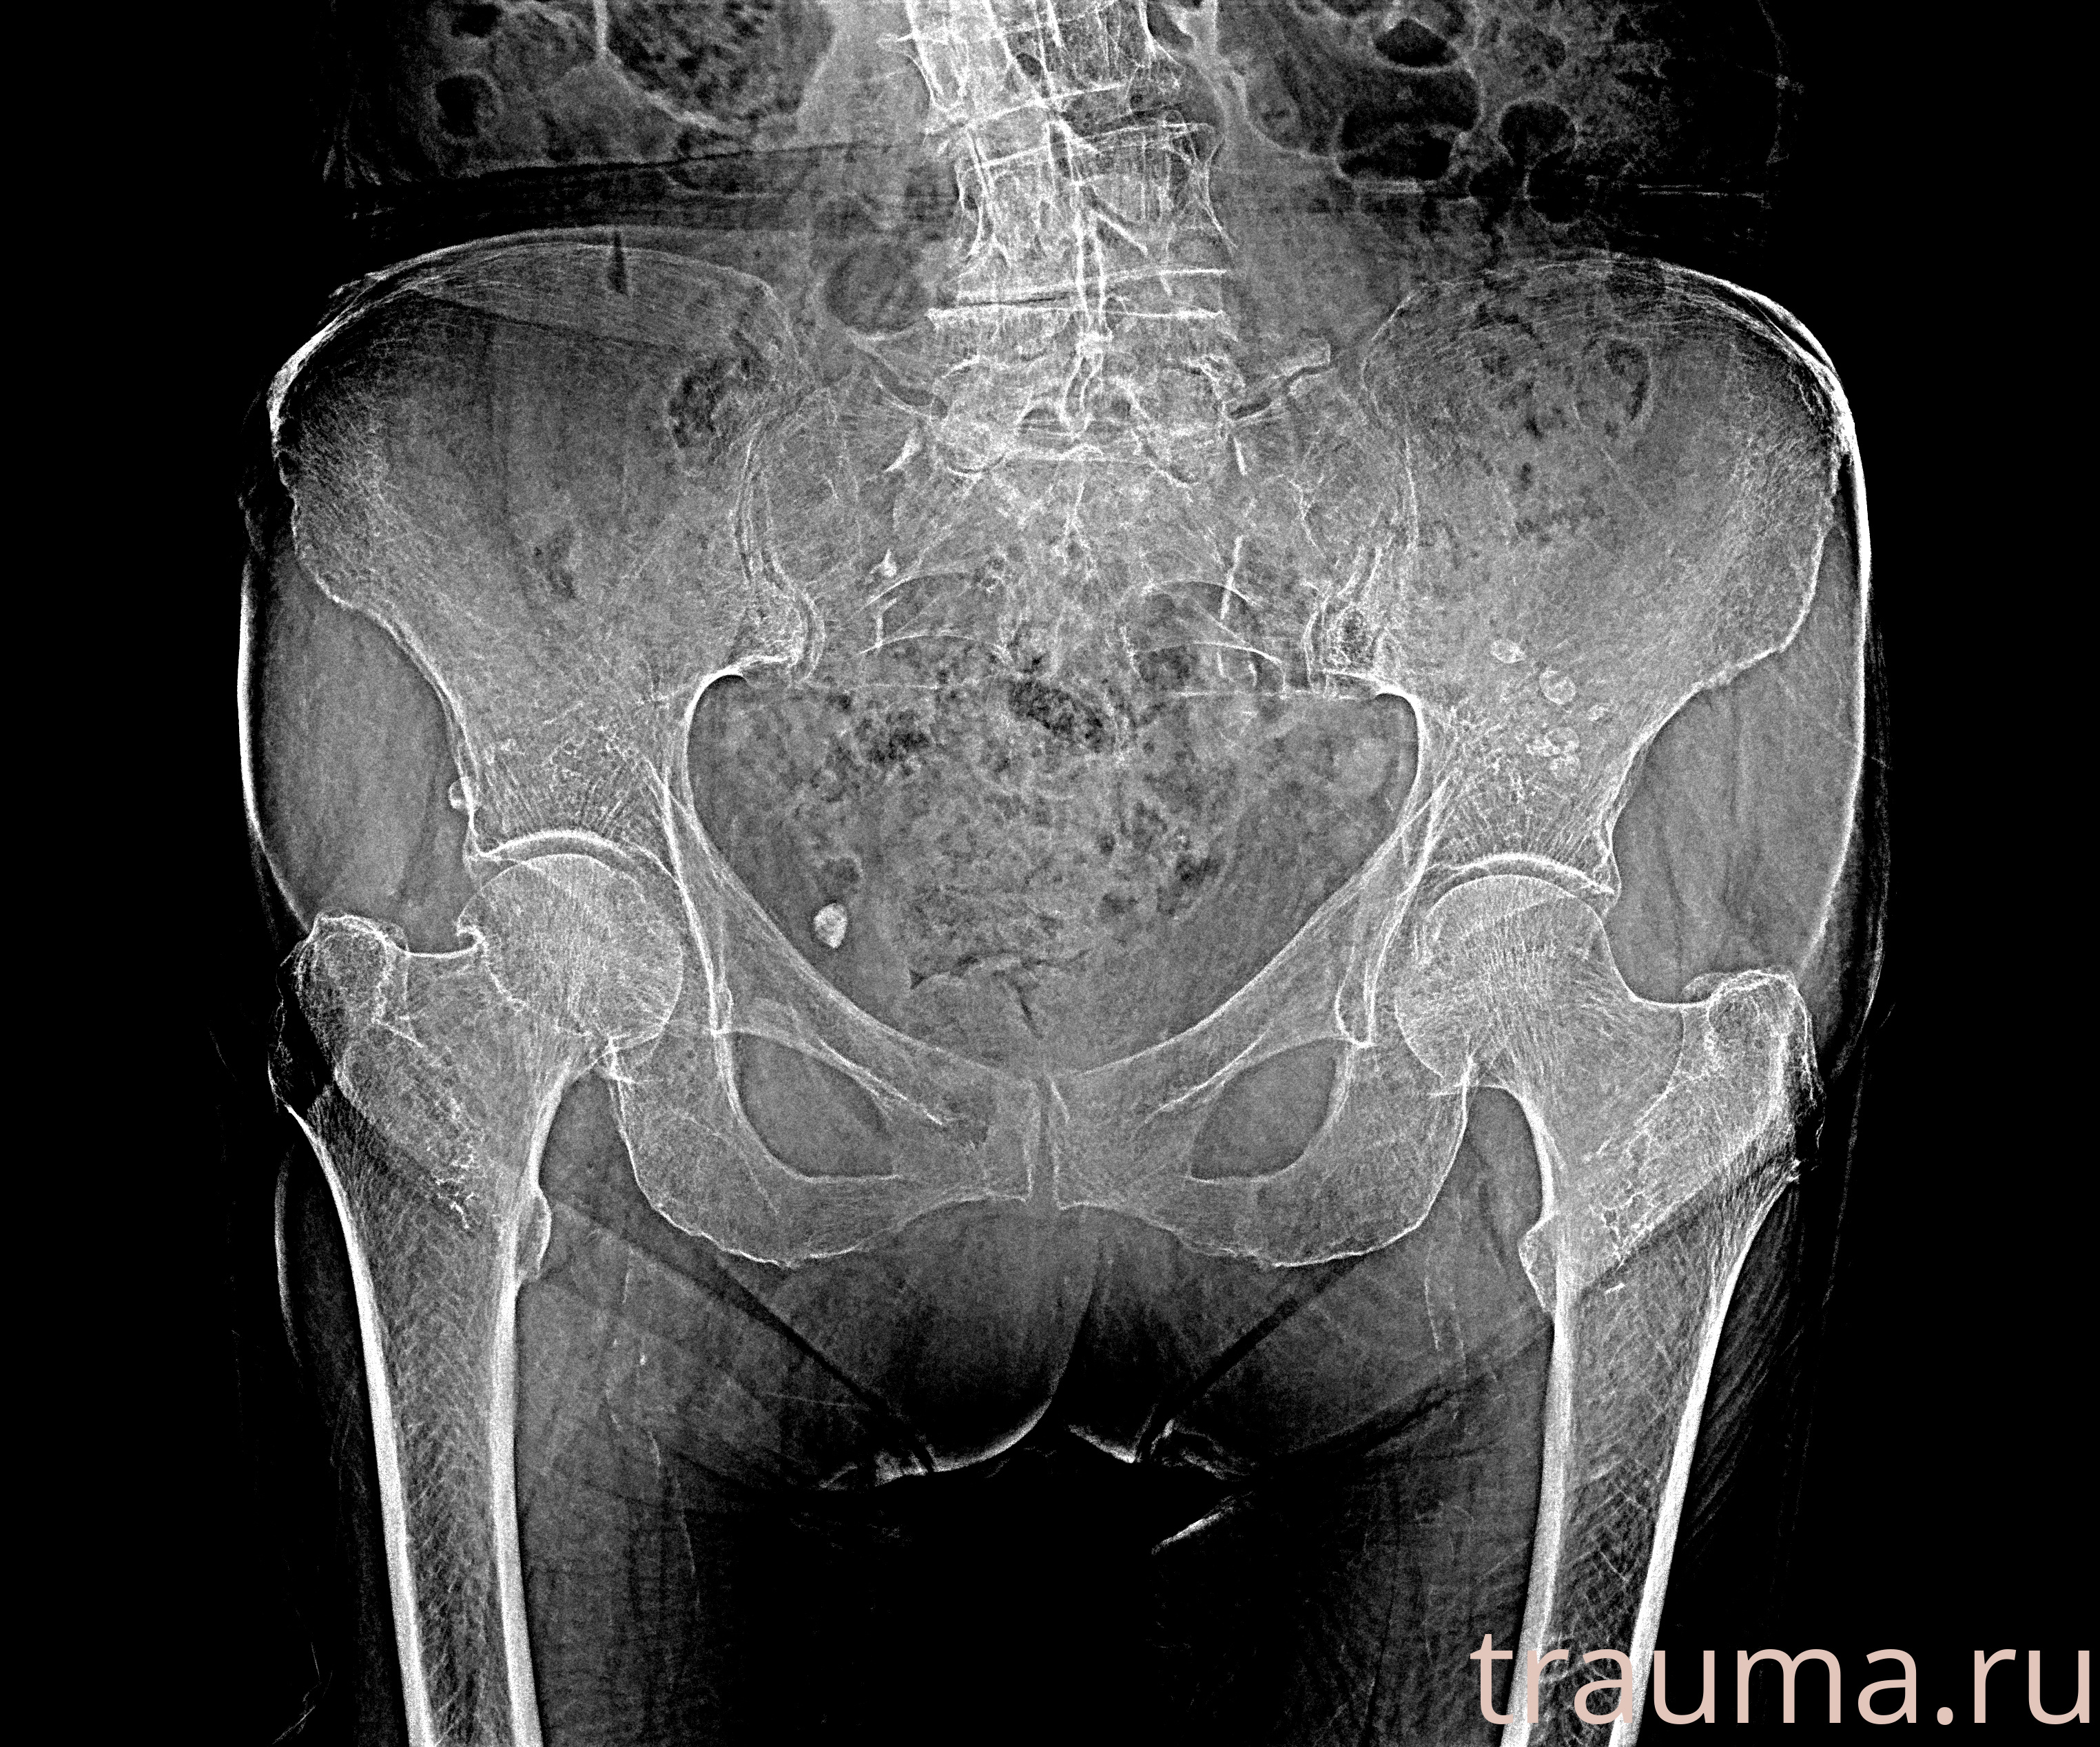

Рентген на дому: по вашему адресу приезжает врач-рентгенолог, травматолог-ортопед с мобильным рентгеновским аппаратом, проводит диагностику травмы или заболевания, делает необходимые рентгенограммы, дает рекомендации по дальнейшему лечению. Получить качественные снимки в домашних условиях возможно благодаря уникальной методике, разработанной МосРентген Центром для института  Склифосовского